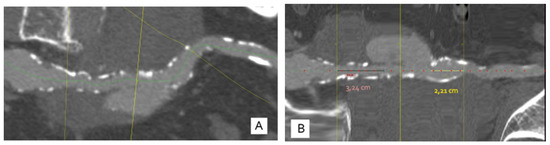

2.2. Case Report II